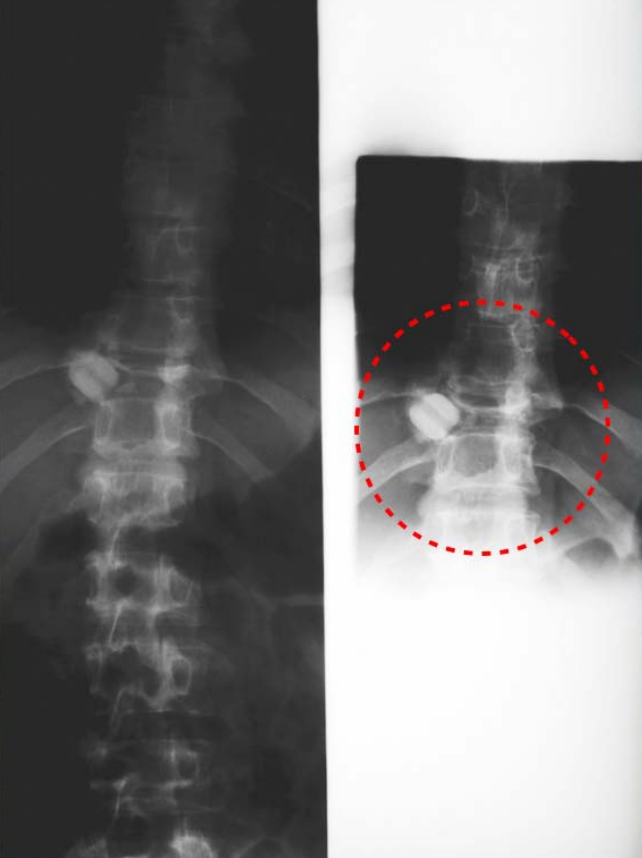

Figure3